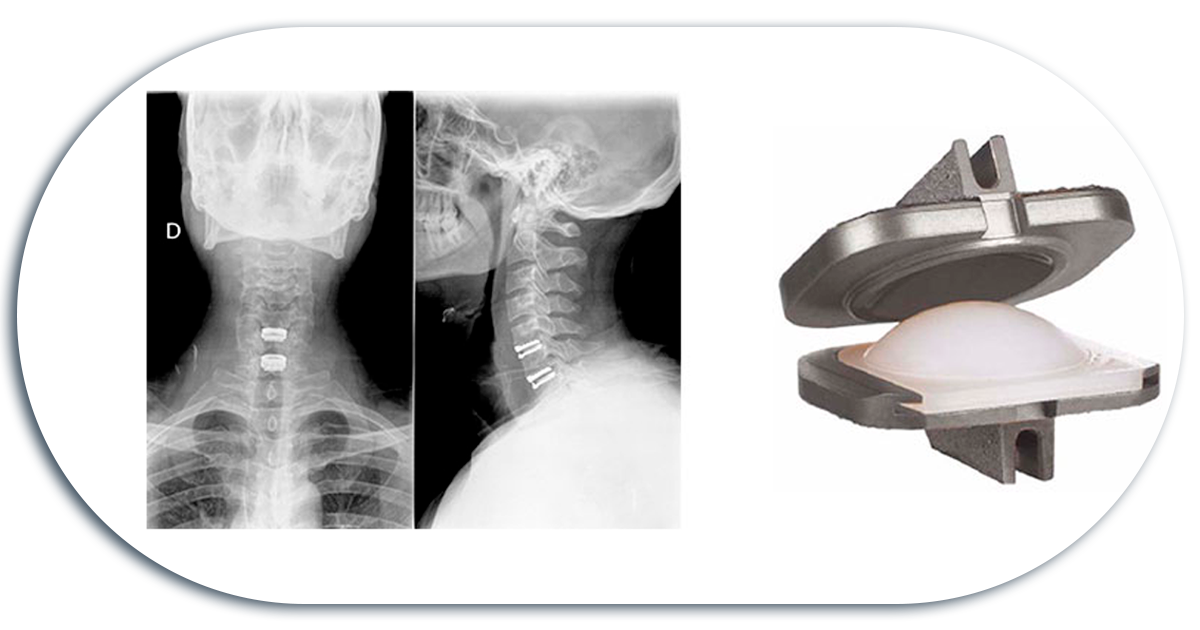

Arthroplasty / Disc Replacement

Disc replacements are used to preserve movement. They allow mobility of the treated area in all axes, such as flexion, extension, rotation, and lateral flexion.

Not all patients are candidates for disc replacement, as all the characteristics of the affected area must be considered.